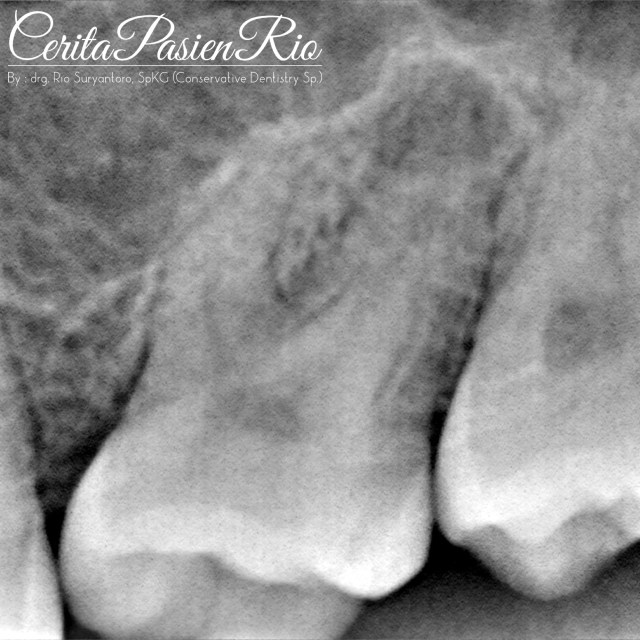

pas saya lihat, saya langsung berpikir bahwa ini kasus crack. kemudian saya lakukan foto rontgen. lalu begini hasilnya.

tampak di bagian apikal gigi molar satu rahang atas kiri terdapat radiousensi. perkusinya positif, dan vitalitas juga positif..